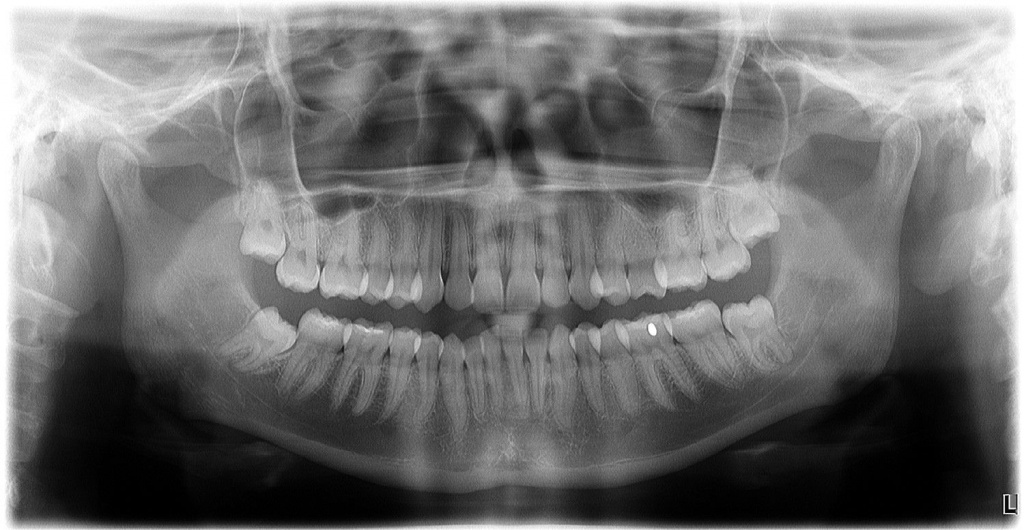

Примеры ортопантомограмм и их анатомия

Раздел: Фотоэссе